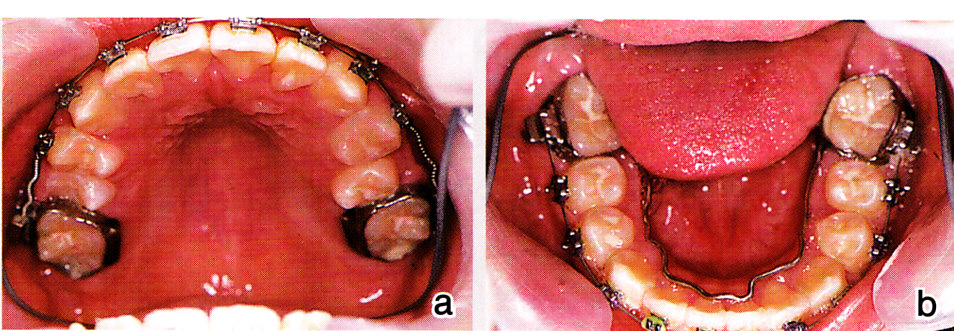

側方歯群の交換時期にはリンガルアーチを装着し、リーウェイスペースを失わないようにしました(図13)。そして、ダイレクトボンドによる歯牙移動を行いました(図14)。混合歯列期における積極的な拡大により、抜歯症例となるのを回避できました(図15)。

図15 a~c:18歳 下顎前歯に少し乱れが出ているが、臼歯のアップライトが不十分なためと思われる